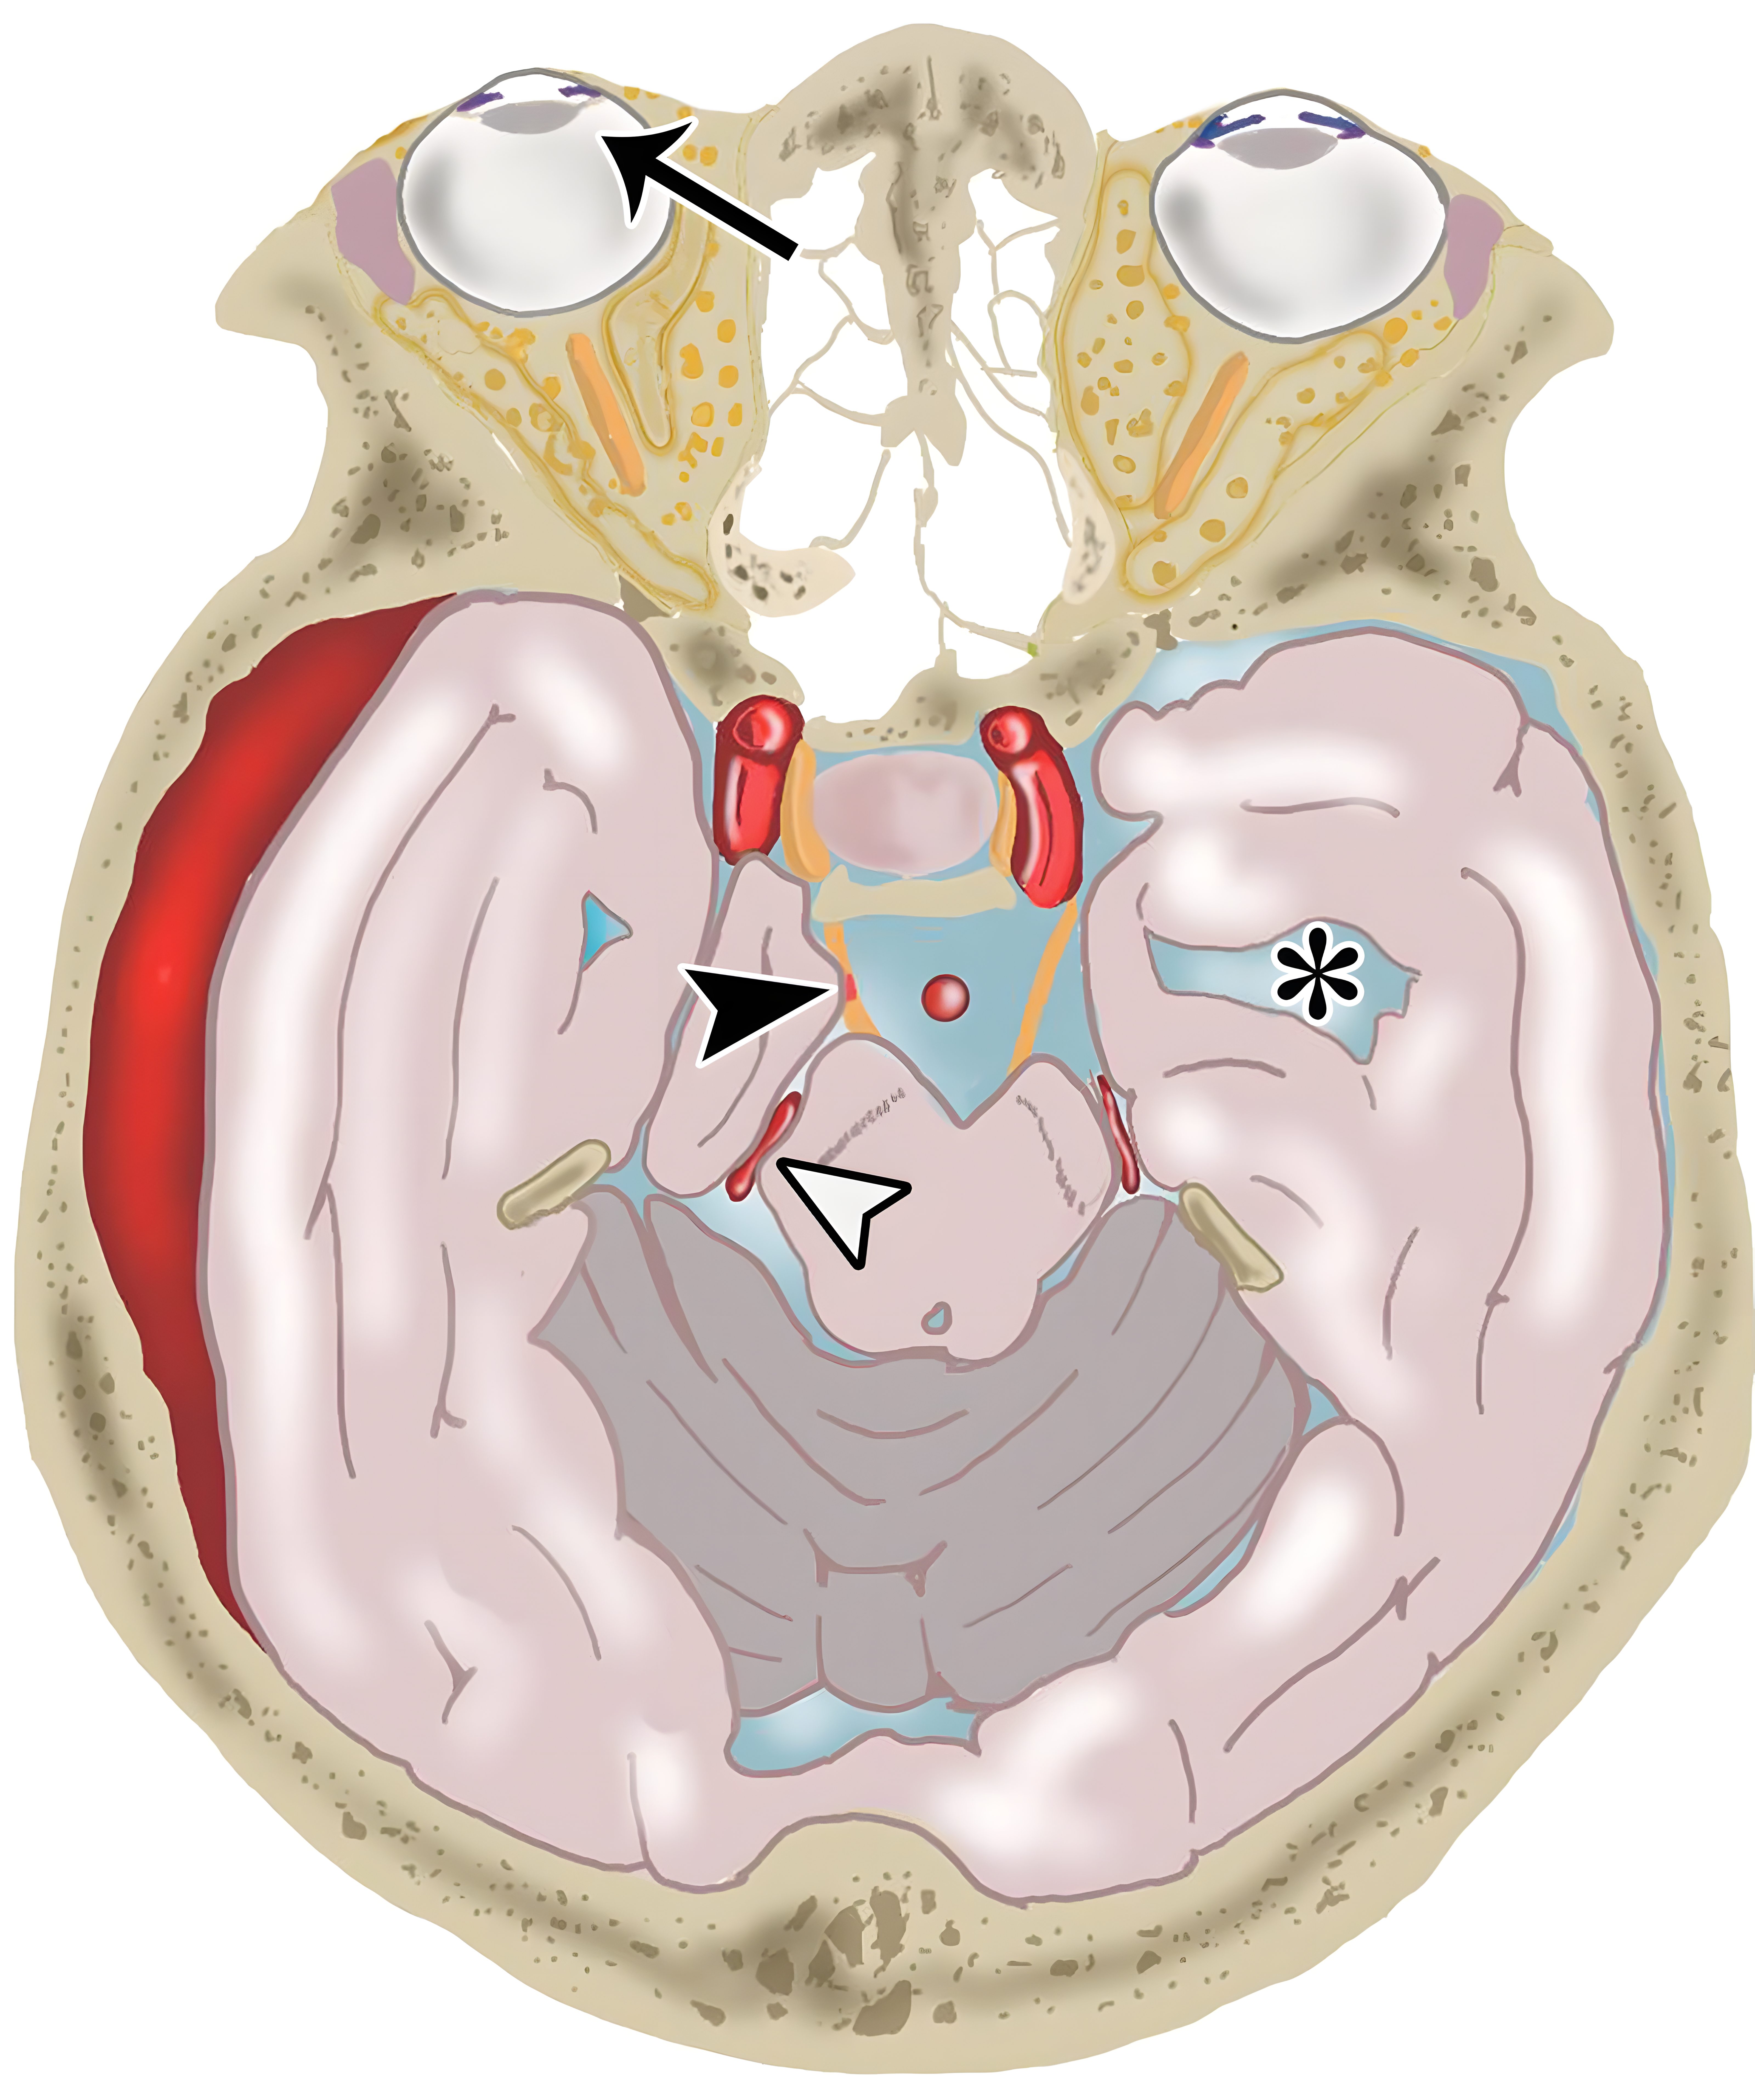

7fc5fed79858f9b47f5b45469c50c241.jpg

横向下降性小脑幕裂孔疝的示意图,伴大脑后动脉受压(白色短箭头),动眼神经受压(黑色短箭头),注意同侧瞳孔扩张(黑色长箭头),对侧侧脑室颞角扩张(*)。